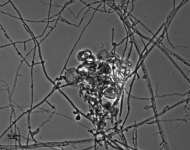

| Species Name: | Blastomyces helicus |

| Synonyms: | Emmonsia helica |

| Taxonomy: | FUNGI Ascomycota, Eurotiomycetes, Onygenales, Ajellomycetaceae |

| Substrate: | pleural fluid from liver transplant patient who died of fungemia, septic shock and pneumonia; isolated twice from blood and pleural effusion |

| Characters: | HUMAN/ ANIMAL PATHOGEN fungal pneumonia in immunosuppressed patient - (Click for publications citing UAMH 11294) |